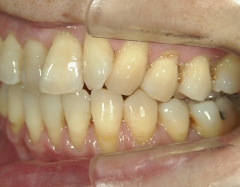

矯正歯科 治療前矯正歯科 治療前

64歳女性 浜松市中区在住

治療期間 7カ月

矯正歯科 治療前